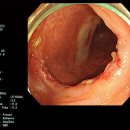

검사 결과가 비슷하여 감별이 어려운 경우가 많다. 장결핵의 경우 내시경 검사상 크론병에서 보이는 세로방향의 깊은 종주궤양과는 달리 장의 주행방향에 수직으로 발생하는 고리모양의 횡행궤양이 보이며, 4분절 이하의 침범, 가성 용종 및 궤양 반흔...